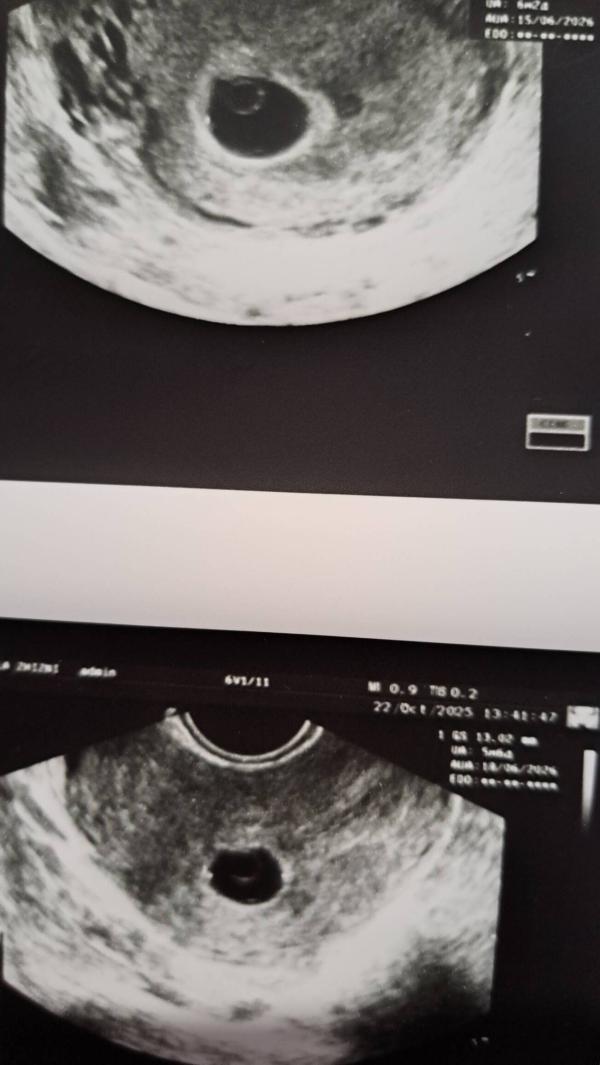

Первые два фото 22.10, последние два фото сегодня. Овуляция 13.09 была, отслежена и подтверждена. По месячным срок 8.5.

Добавлю. Врач с отпуска 5 ноября выходит, перед абортом узи все равно делают, с одними этими я убирать не буду ничего, свд 21, у меня еще целых 4мм есть до точного диагноза. Хгч еще раз сдам в динамике с завтрашнего дня точно. Меня просто интересует, до какого размера пя делают медикаментозный аборт, чтобы меньше вмешательства в матку было, если уж совсем никак и тогда не появится.

Так и не бегу прям завтра, но жм уже 2 недели как есть, а намека на эмбрион нет вообще. Даже с поздней визуализацией у меня надежд 0.1%

Сочувствую... Сама недавно столкнулась с похожей ситуацией. Почему-то сказали, что вакуум лучше для меня, когда я с просила про МА. 18 мм был СВД.

@safronova94 мой врач из отпуска только 5 ноября выйдет, перед абортом все равно узи есть, так что там последняя надежда и все. Но я уже особо не надеюсь. Что в прошлый раз, что сегодня, сказали что жм слишком большой и это плохой признак, далее уже искали эмбрион и не нашли. Но в любом случае, я расстроена, но не смертельно. Если эмбрион не развивался, значит не жизнеспособен.